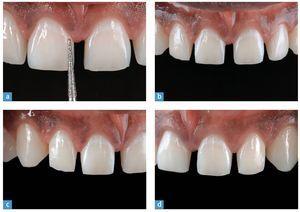

El acabado y el pulido de la preparación son el requisito para obtener unos modelos precisos. Este paso de trabajo se lleva a cabo con un diamante fino, serie roja (n.º 8856 018, Brasseler). Éste posee la misma forma y el mismo diámetro que la fresa utilizada durante la preparación. El acabado de la preparación elimina todos los rasguños de la fresa previamente empleada (fig. 18). En la figura 19 se ofrece una vista detallada de la preparación extremadamente respetuosa. Tras el acabado se utilizan de nuevo las llaves de silicona para verificar la preparación (fig. 20). Los caninos se pulen únicamente para eliminar eventuales zonas retentivas que pudieran obstaculizar el ajuste de las carillas parciales.

Fig. 19. Tomas de detalle de la preparación de carilla extremadamente respetuosa. a Vista de los dientes anteriores superiores centrales antes de la operación; b el rebajado de la altura proximal de la forma; c después del rebajado proximal; d el inicio de la reducción; e la preparación terminada tras el pulido.